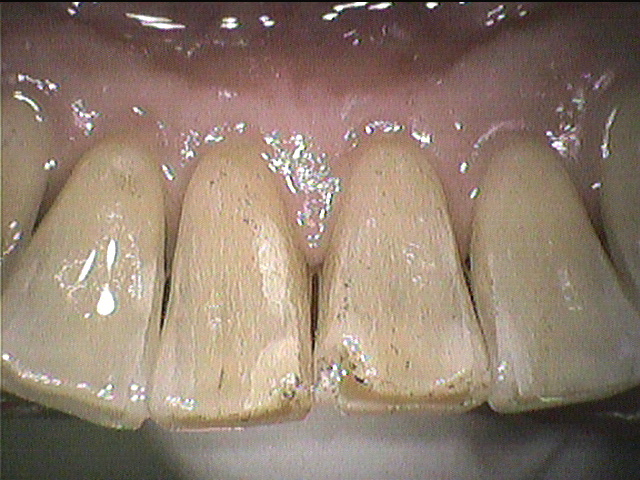

クリーニング後

下の前歯と上の前歯の裏側の写真です。

ステインに加えて歯石もついていましたが、しっかり除去し綺麗になりました。